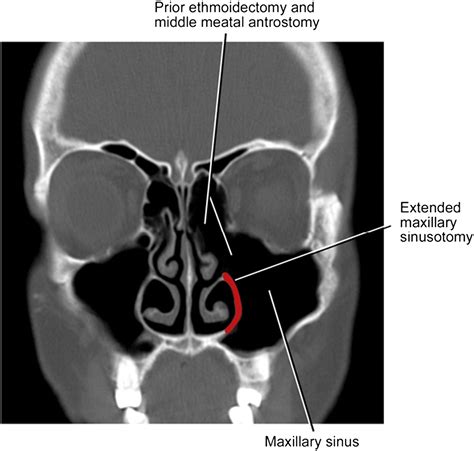

• Pre-Surgical Planning: Detailed imaging to plan for sinus surgery.

Treatment Options Based on Mxailliary Sinus CT Scan Results

• Surgery: Surgical procedures to remove polyps, correct structural issues, or drain infected sinuses.